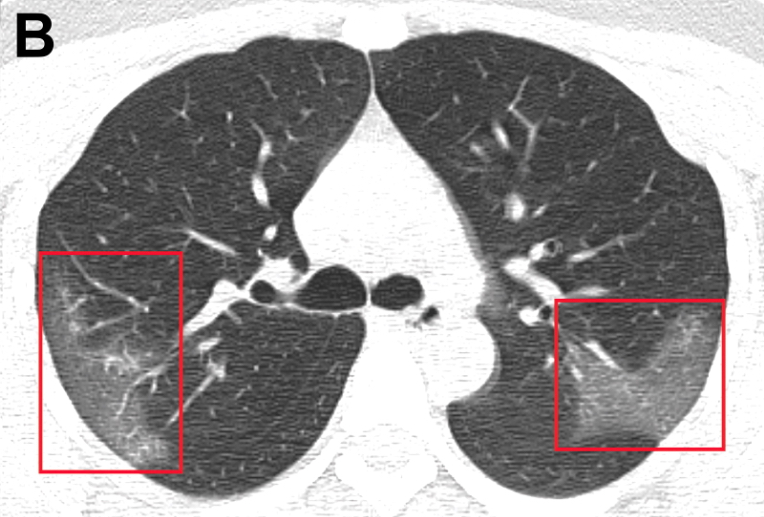

Cuadro febril con fatiga y tos seca, evoluciona a disnea en 5 días; presenta linfopenia, LDH elevada y tiempo de protrombina prolongado; tomografía con opacidad bilateral en vidrio esmerilado. El 26% requirió cuidados intensivo y el 4,3% falleció. JAMA, 7 de febrero de 2020